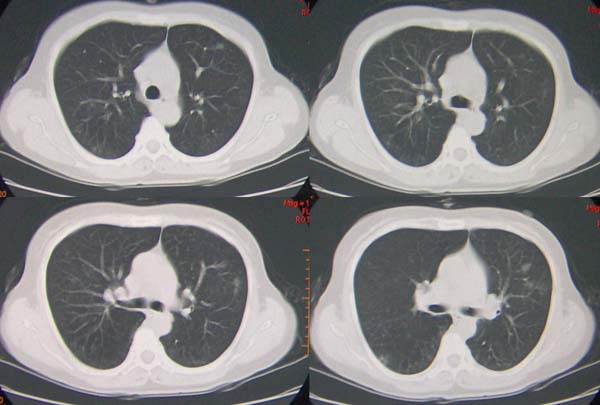

标题: CT9509:女,50岁,咳嗽,发热,38度, [打印本页]

标题: CT9509:女,50岁,咳嗽,发热,38度,

左肺下叶支气管呈囊状扩张。考虑支扩。

左肺下叶支气管呈囊状扩张。考虑支扩。胸膜肥厚\\粘连,建议增强除外肺隔离症.

左肺上叶小片状病灶密度底,左下叶见多发小囊状病灶,周围透光增强无纹理,沿左侧膈肌旁见条带状病灶边界清晰,

1左肺上叶炎症,左下支气管扩张伴感染,肺隔离征待除外,2肺大泡,3左下叶内基底段不张?

肺隔离症伴支扩(肺外型)或肺发育不良。

1,左肺下叶支气管扩张?

2,肺隔离症?

左肺舌叶及右肺下叶背段斑片状低密度影,左肺下叶内基底段网格状阴影,周围肺野透亮度增高,结合临床咳嗽、发热,38度,无咯血及反复感染病史,考虑双肺炎症,左下肺发育不良。建议抗炎治疗后复查或增强与左下肺隔离症鉴别。